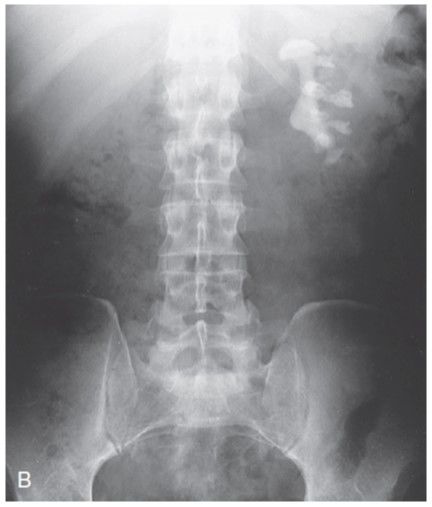

3. RX

1. KUB, SE EXAMINAN CUIDADOSAMENTE

1. Anormalidades del esqueleto, Bordes suaves del tejido hepatico, bazo y psoas, patrones de gas en el intestino y calcificaciones

1. Examinar tamaño renal

1. El riñón izquierdo es un poco superior a l derecho

2. Uréter

1. Anteriores al psoas en L3 y L5